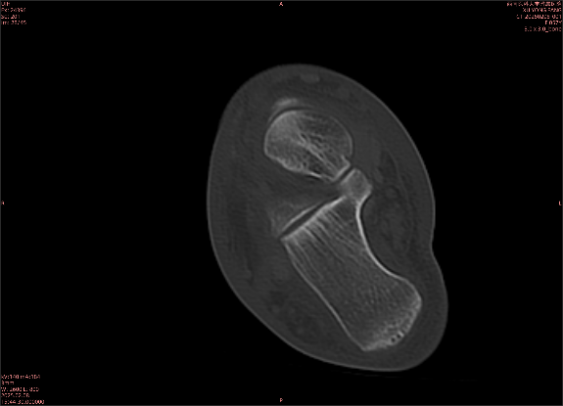

舉例圖像

圖1

專業(yè)解釋看不懂沒關(guān)系,大家看圖1和圖2就可以了,這是同一個(gè)患者跟骨的磁共振和CT圖像,圖1的紅色箭頭指示的黑線就是磁共振圖像顯示的骨折線,一目了然。而對(duì)比圖2的CT圖像上并未顯示異常。